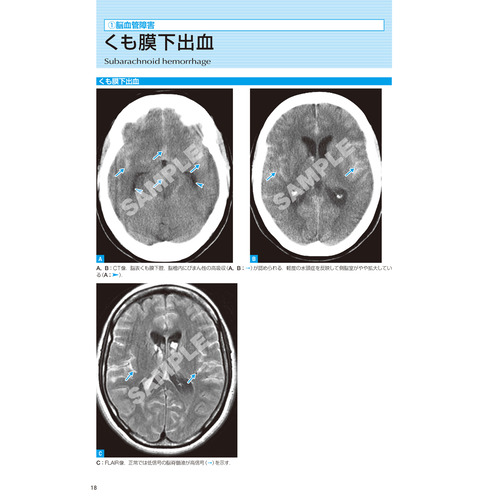

Ⅰ.脳神経(22疾患)脳血管障害,外傷/認知性疾患/脱髄変性・代謝性疾患/炎症性疾患/脳腫瘍